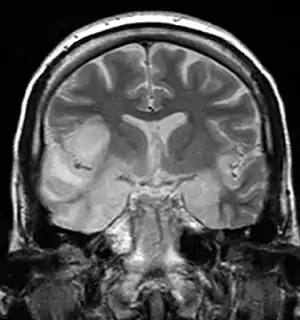

| Herpesviral encephalitis and herpesviral meningitis | Herpes simplex encephalitis (HSE) is a rare life-threatening condition that is thought to be caused by the transmission of HSV-1 either from the nasal cavity to the brain's temporal lobe or from a peripheral site on the face, along the trigeminal nerve axon, to the brainstem.[18][19][20][21] Despite its low incidence, HSE is the most common sporadic fatal encephalitis worldwide. HSV-2 is the most common cause of Mollaret's meningitis, a type of recurrent viral meningitis. | ![]() |